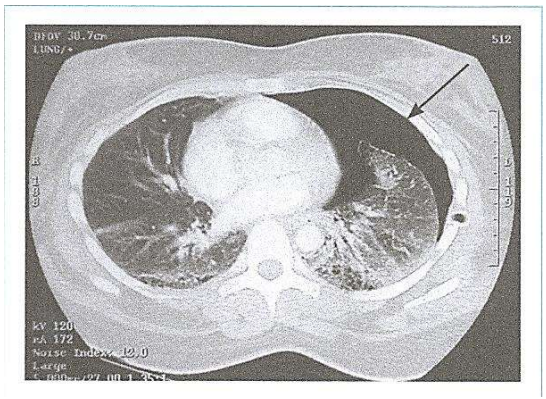

A tomografia de tórax é um exame capaz de identificar alterações morfofuncionais, contribuindo para o

diagnóstico e acompanhamento das patologias.

A imagem é sugestiva de qual entidade clínica?